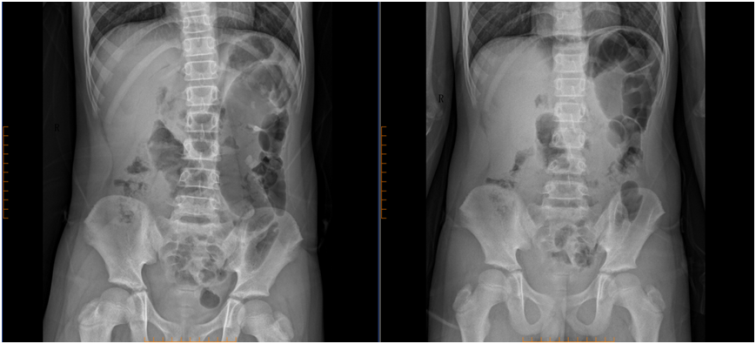

• 腹部立位片显示气腹(腹腔内出现游离气体)、部分肠管明显扩张,这是胃肠道穿孔的典型信号

• 彩超提示腹腔积液、脐周淋巴结肿大,说明腹腔内已有感染

• 血常规显示中性粒细胞比例高达87.4%,提示严重细菌感染

“孩子已经出现了弥漫性腹膜炎的表现,再晚几个小时,就可能发展成感染性休克,危及生命。”接诊胡铭惠主治医师说,结合症状和检查结果,确诊为胃穿孔伴急性腹膜炎,必须立即手术。